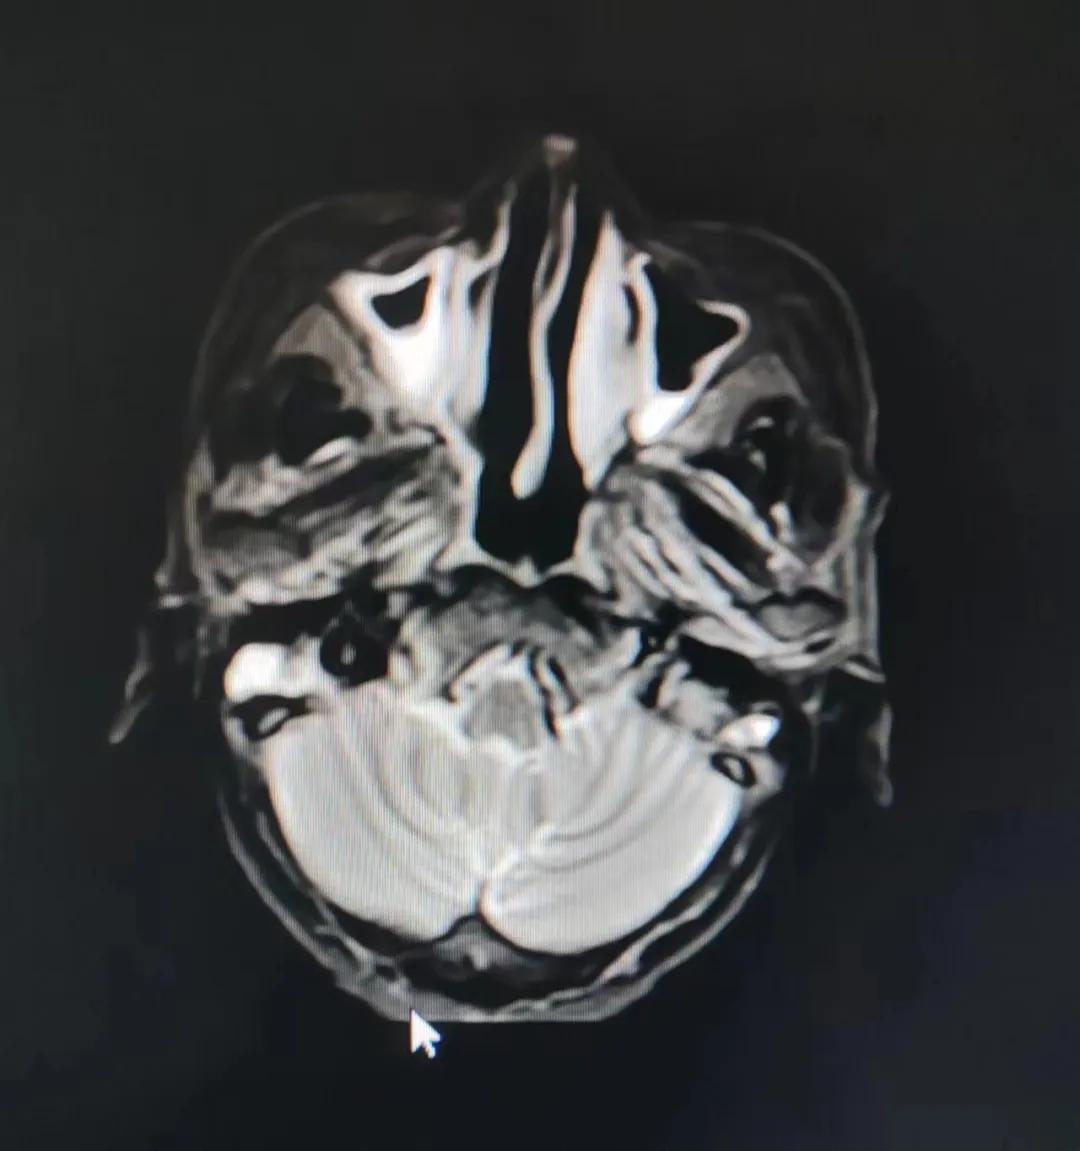

治療前

考慮到患者年齡較大、體質(zhì)差,手術(shù)難度大,且常規(guī)的放射治療難以保護(hù)患者晶體造成患者雙眼視力損傷,放療團(tuán)隊(duì)以最快的速度制定了精準(zhǔn)放射治療方案并開始為其實(shí)施治療。僅僅數(shù)日后,老人腫塊出血即得到控制,腫塊明顯縮小,放療20次后腫塊迅速縮?。?/div>

治療后

放療結(jié)束,除了放療處的皮膚輕微放射性皮炎外,基本沒有什么不良反應(yīng)。復(fù)查發(fā)現(xiàn),鼻腔淋巴瘤已不可見,目前患者已康復(fù)出院。